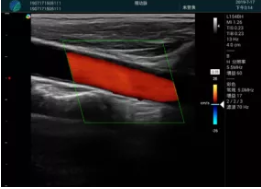

頸動脈血流充盈飽滿,無外溢

肝內血管顯示清晰,血流敏感無外溢